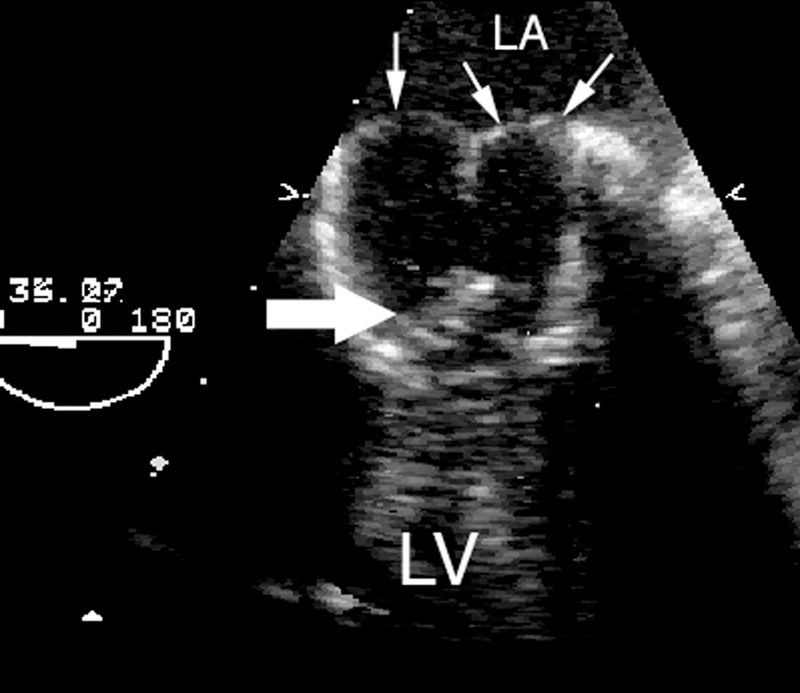

فحوصات تشخيصية لبعض امراض القلب والشرايين التاجية